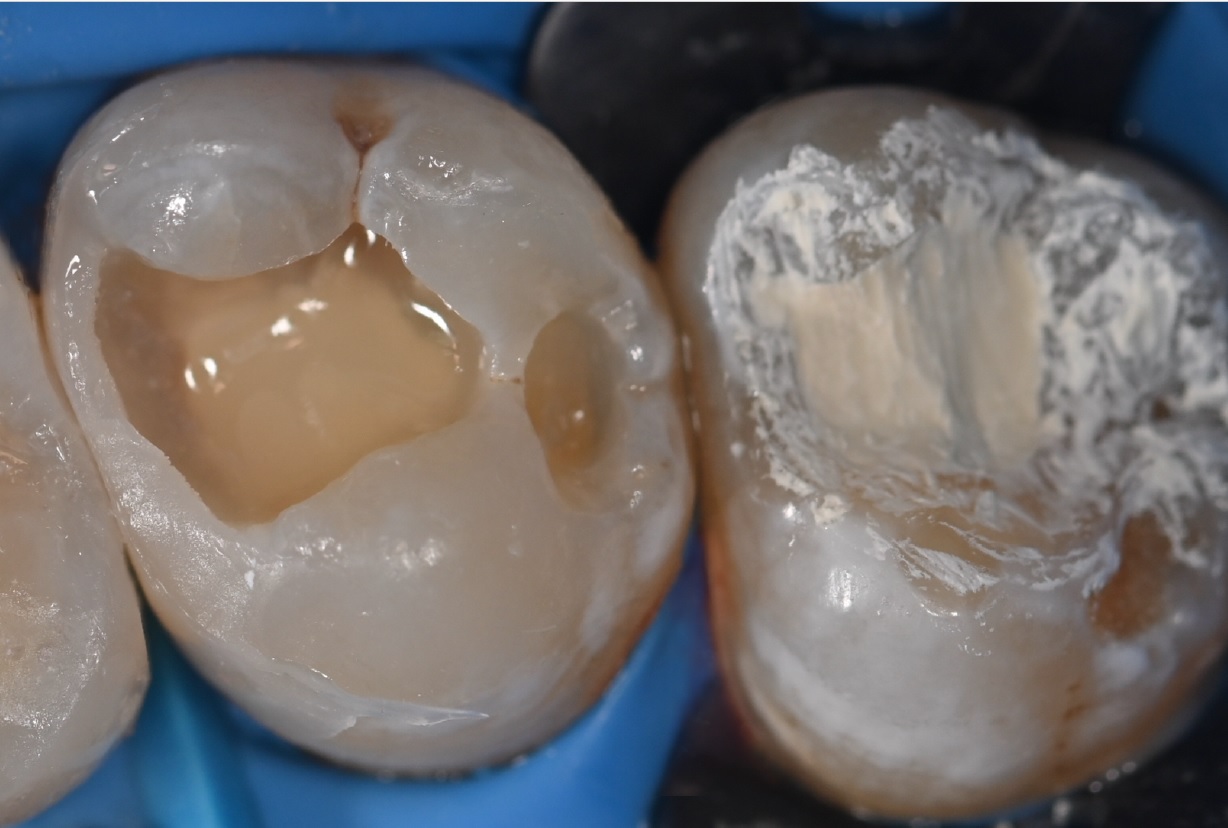

Εικ. 6: Μόλις έπηξε το υλικό, η αδαμαντίνη αδροποιήθηκε επιλεκτικά με ορθοφωσφορικό οξύ για 20 δευτερόλεπτα.

Εικ. 7: Η εικόνα δείχνει την τυπική εμφάνιση μιας σωστά αδροποιημένης αδαμαντίνης. Επιπλέον, είναι δυνατό να παρατηρηθεί ότι κατά τη φάση έκπλυσης με οξύ, το σκληρό πια Biodentine XP δεν διαλύθηκε και παρέμεινε άθικτο. Στη συνέχεια, εφαρμόστηκαν δύο στρώσεις ενός συγκολλητικού παράγοντα επόμενης γενιάς (3M™ Scotchbond™ Universal Plus Adhesive, Solventum) σε ολόκληρη την επιφάνεια της κοιλότητας. Μετά το απαλό φύσημα με αέρα, ο συγκολλητικός παράγοντας φωτοπολυμερίστηκε.